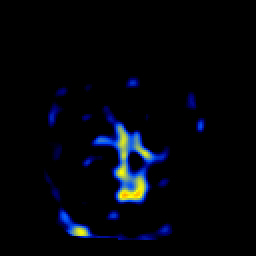

SPECT TL Study #1 -- Slice #32

[Home][Help][Clinical][Tour 1][Tour 2][Tour 3] Slice 32